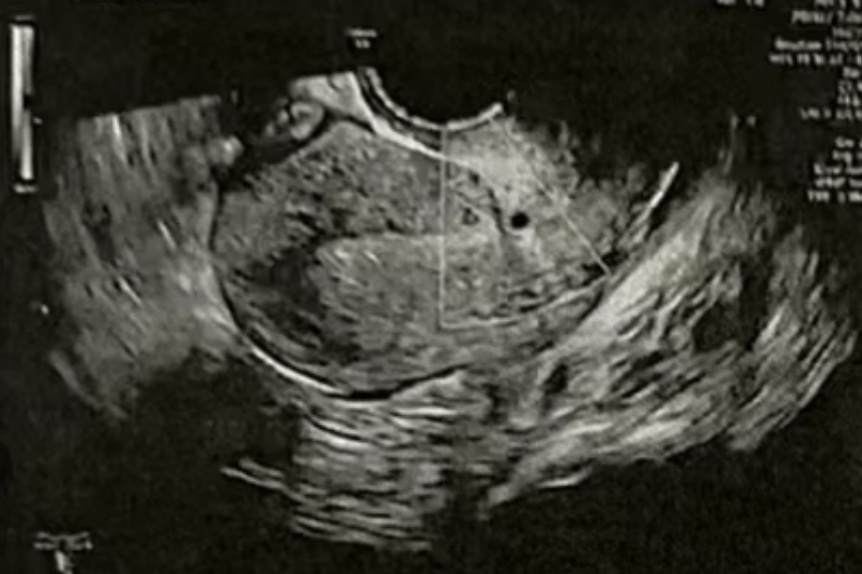

• Pre-Irrigation灌洗前:

• Pre-Irrigation灌洗后: